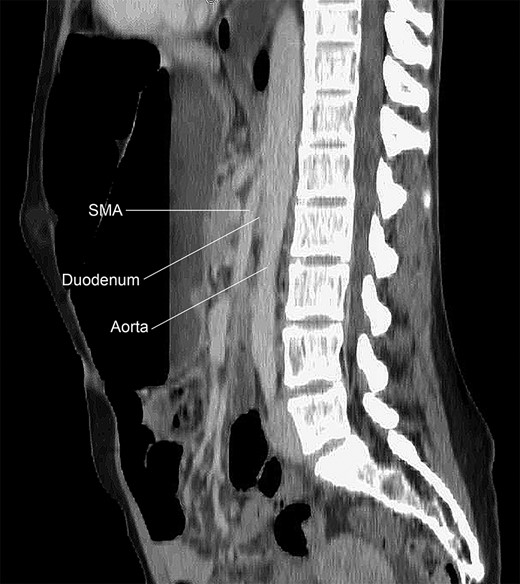

Immediately prior to presentation, the patient experienced another episode of nausea, abdominal pain, distention, and diarrhea. Again, the patient denied any weight loss and did not exhibit signs or symptoms of systemic infection. Computed tomography (CT) of the abdomen and pelvis with oral and intravenous contrast as well as an upper GI series demonstrated a significantly dilated duodenum with a sharp transition to collapsed small bowel (Fig. 1). CT also demonstrated an acutely angulated SMA with compression of the duodenum between the SMA and the aorta (Fig. 2). Endoscopic evaluation did not demonstrate any evidence of mechanical obstruction of the duodenum.

CT of the abdomen and pelvis demonstrating an acutely angulated SMA with compression of the duodenum between the SMA and the aorta.